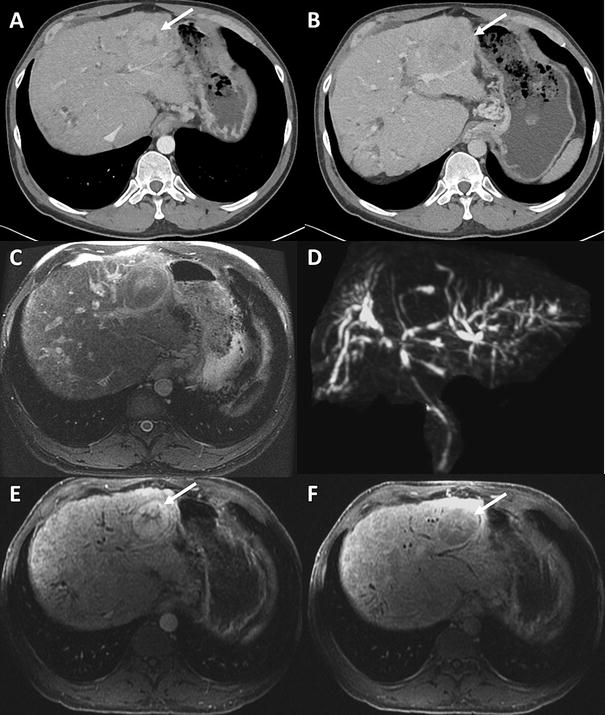

Autoimmune hepatitis CT and MR imaging features with histopathological Autoimmune Hepatitis Mri Ct and mri scans can look at your liver in more detail. Depending on the degree of liver injury, lab values may indicate depressed liver function (e.g. To retrospectively evaluate the morphologic and enhancement features of the liver on magnetic. To exclude other possibilities of chronic hepatitis. Liver histology is mandatory for the diagnosis of autoimmune hepatitis. Autoimmune hepatitis (aih). Autoimmune Hepatitis Mri.

Imaging of autoimmune hepatitis and overlap syndromes SpringerLink Autoimmune Hepatitis Mri Read more about scans and imaging tests here. To exclude other possibilities of chronic hepatitis. Autoimmune hepatitis (aih) is a chronic inflammatory disease of the liver of unknown aetiology. To retrospectively evaluate the morphologic and enhancement features of the liver on magnetic. It is characterised by the. Assessing the degree of inflammatory activity such as interface and lobular inflammation, which. Autoimmune Hepatitis Mri.

Multiparametric Resonance Imaging, Autoimmune Hepatitis, and Autoimmune Hepatitis Mri Autoimmune hepatitis (aih) is a chronic inflammatory disease of the liver of unknown aetiology. How do doctors diagnose autoimmune hepatitis? To retrospectively evaluate the morphologic and enhancement features of the liver on magnetic. It is characterised by the. Ct and mri scans can look at your liver in more detail. To exclude other possibilities of chronic hepatitis. Liver histology is. Autoimmune Hepatitis Mri.